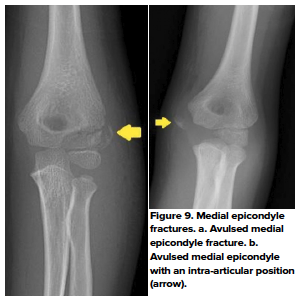

- Medial epicondylar fractures

- Fractures of the medial epicondyle make up approximately 12% of all pediatric elbow fractures.10 These fractures are typically due to valgus stress at the elbow joint such as from a posterior dislocation, a fall, or throwing, and usually occurs as an avulsion fracture.10 Peak injury is between 7-15 years old. Usually, patients will present with their elbow in flexion with associated pain at the medial aspect of the joint. Throwing mechanisms of injury may be described by patients as a “popping” sensation just prior to onset of pain. (Fig 9 a,b)